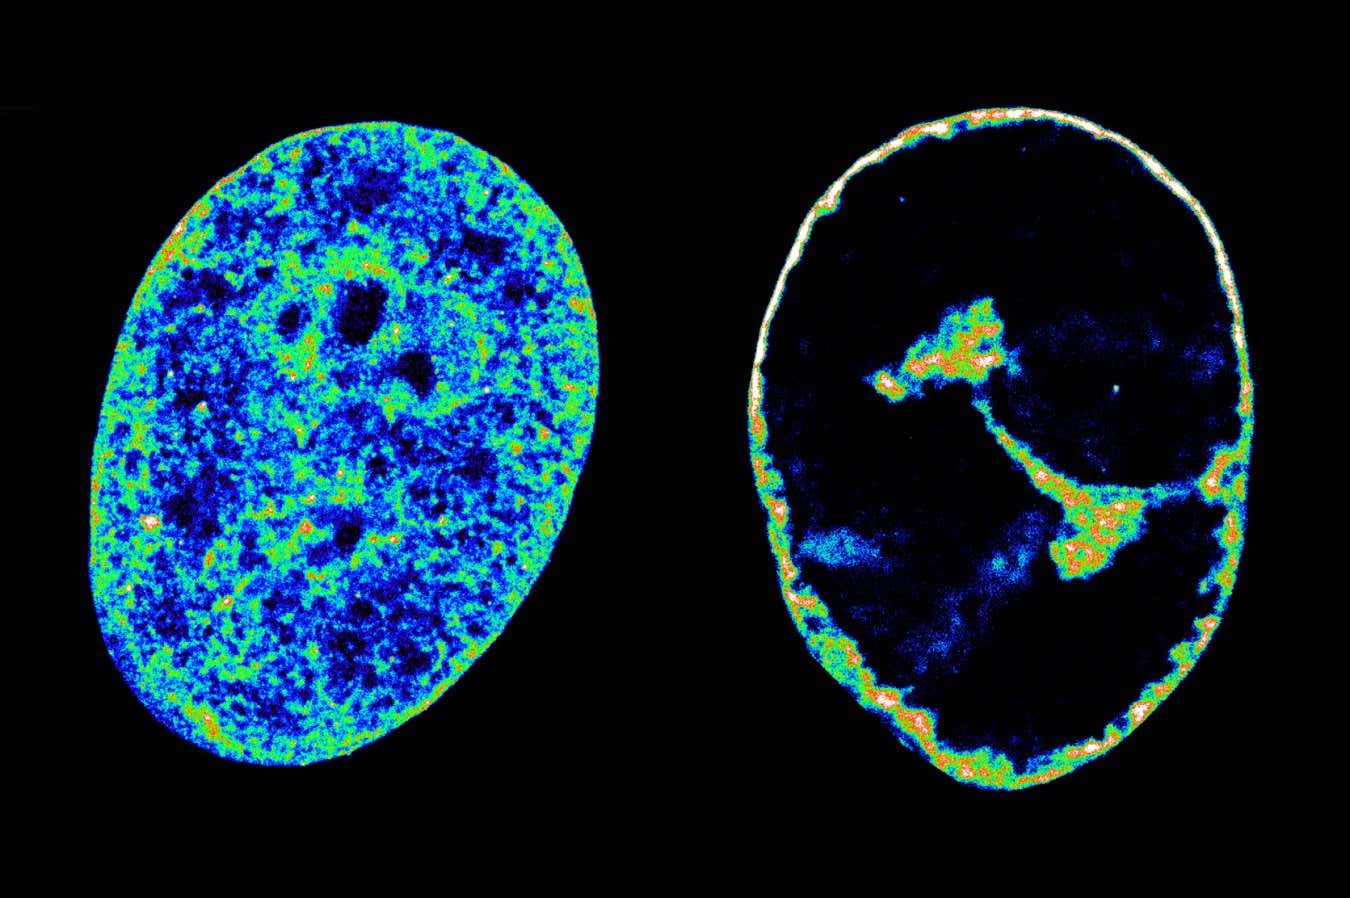

Alzheimer's-related cognitive decline could be slowed by taking as few as 3000 steps a day, possibly due to the effects of regular exercise on brain health newscientist.com/article/250263…

In a study using an Alzheimer’s disease mouse model, researchers found that cannabidiol reduced memory loss and brain abnormalities. The compound worked by enhancing the function of glycine receptors, which help regulate neuronal activity in the brain's… dlvr.it/TL0HHL